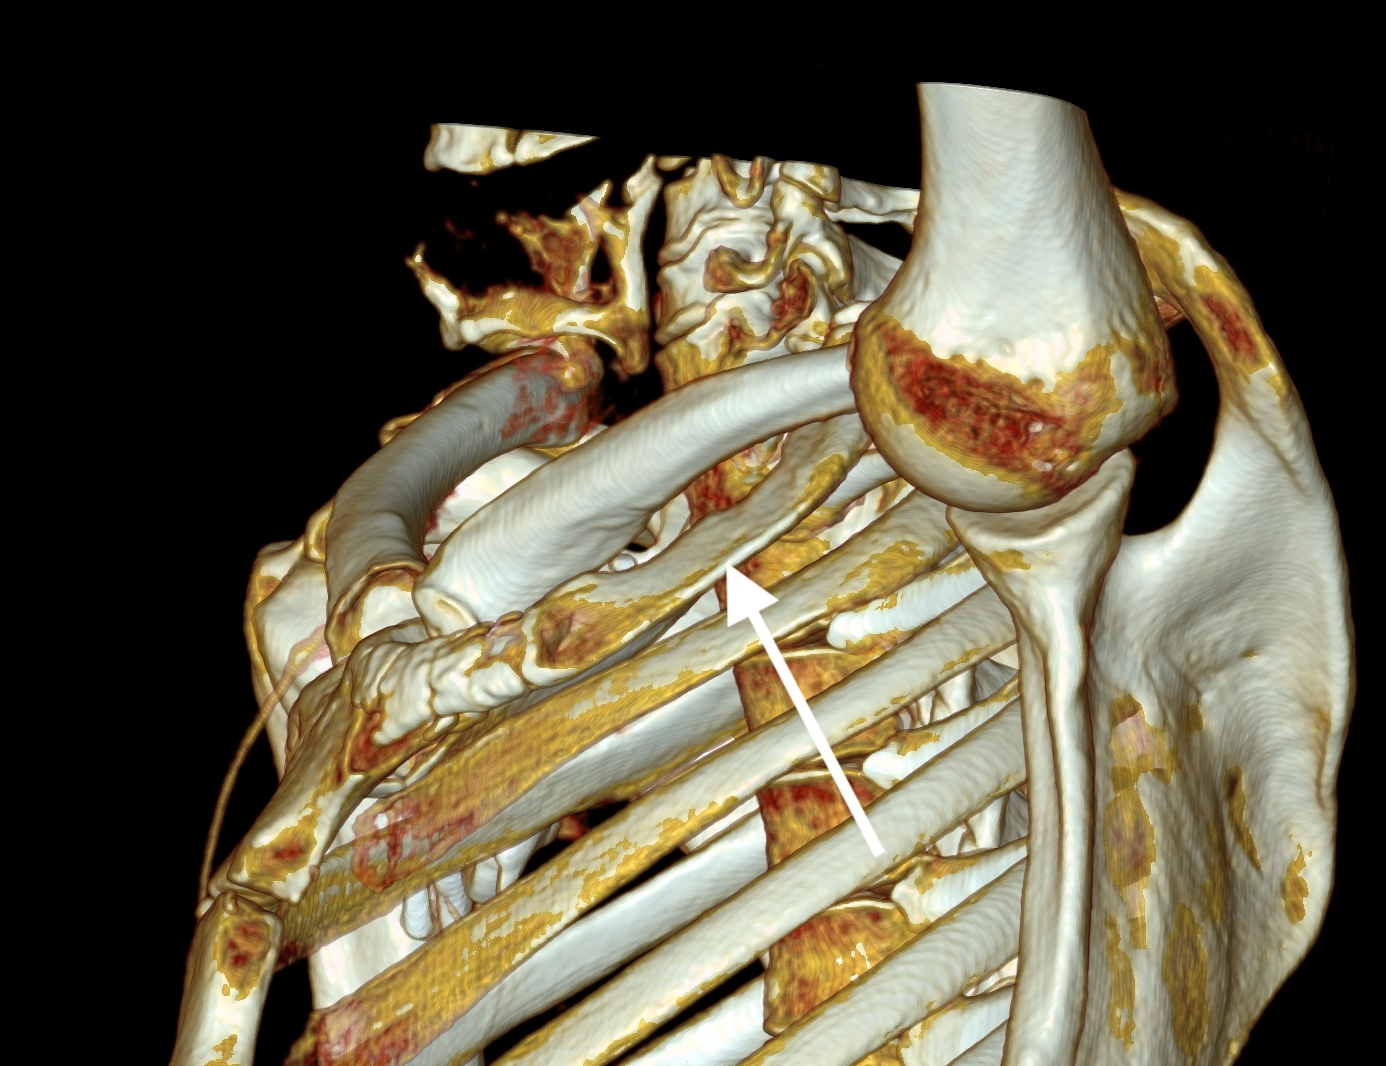

The patient’s first reaction was a dubious expression. After all, in this day and age, isn’t it barbaric to offer to cut out a rib? Why not put a stent there? A CT venogram was obtained showing the subclavian vein occlusion, but we knew that. I use the 3D surface reconstructions extensively as a visual map to determine surgical approach. I remove first ribs through both supraclavicular and transaxillary approaches, choosing one or the other.

The 3D reconstruction of the bones showed that to get to the first rib section underlying the vein, it was best approached via a transaxillary approach. The arrow in the image shows the flare in the first rib where the anterior scalene muscle attaches. Adding muscle shows that in this well muscled patient, getting to the first rib would be a challenge -for the people holding the retractors.